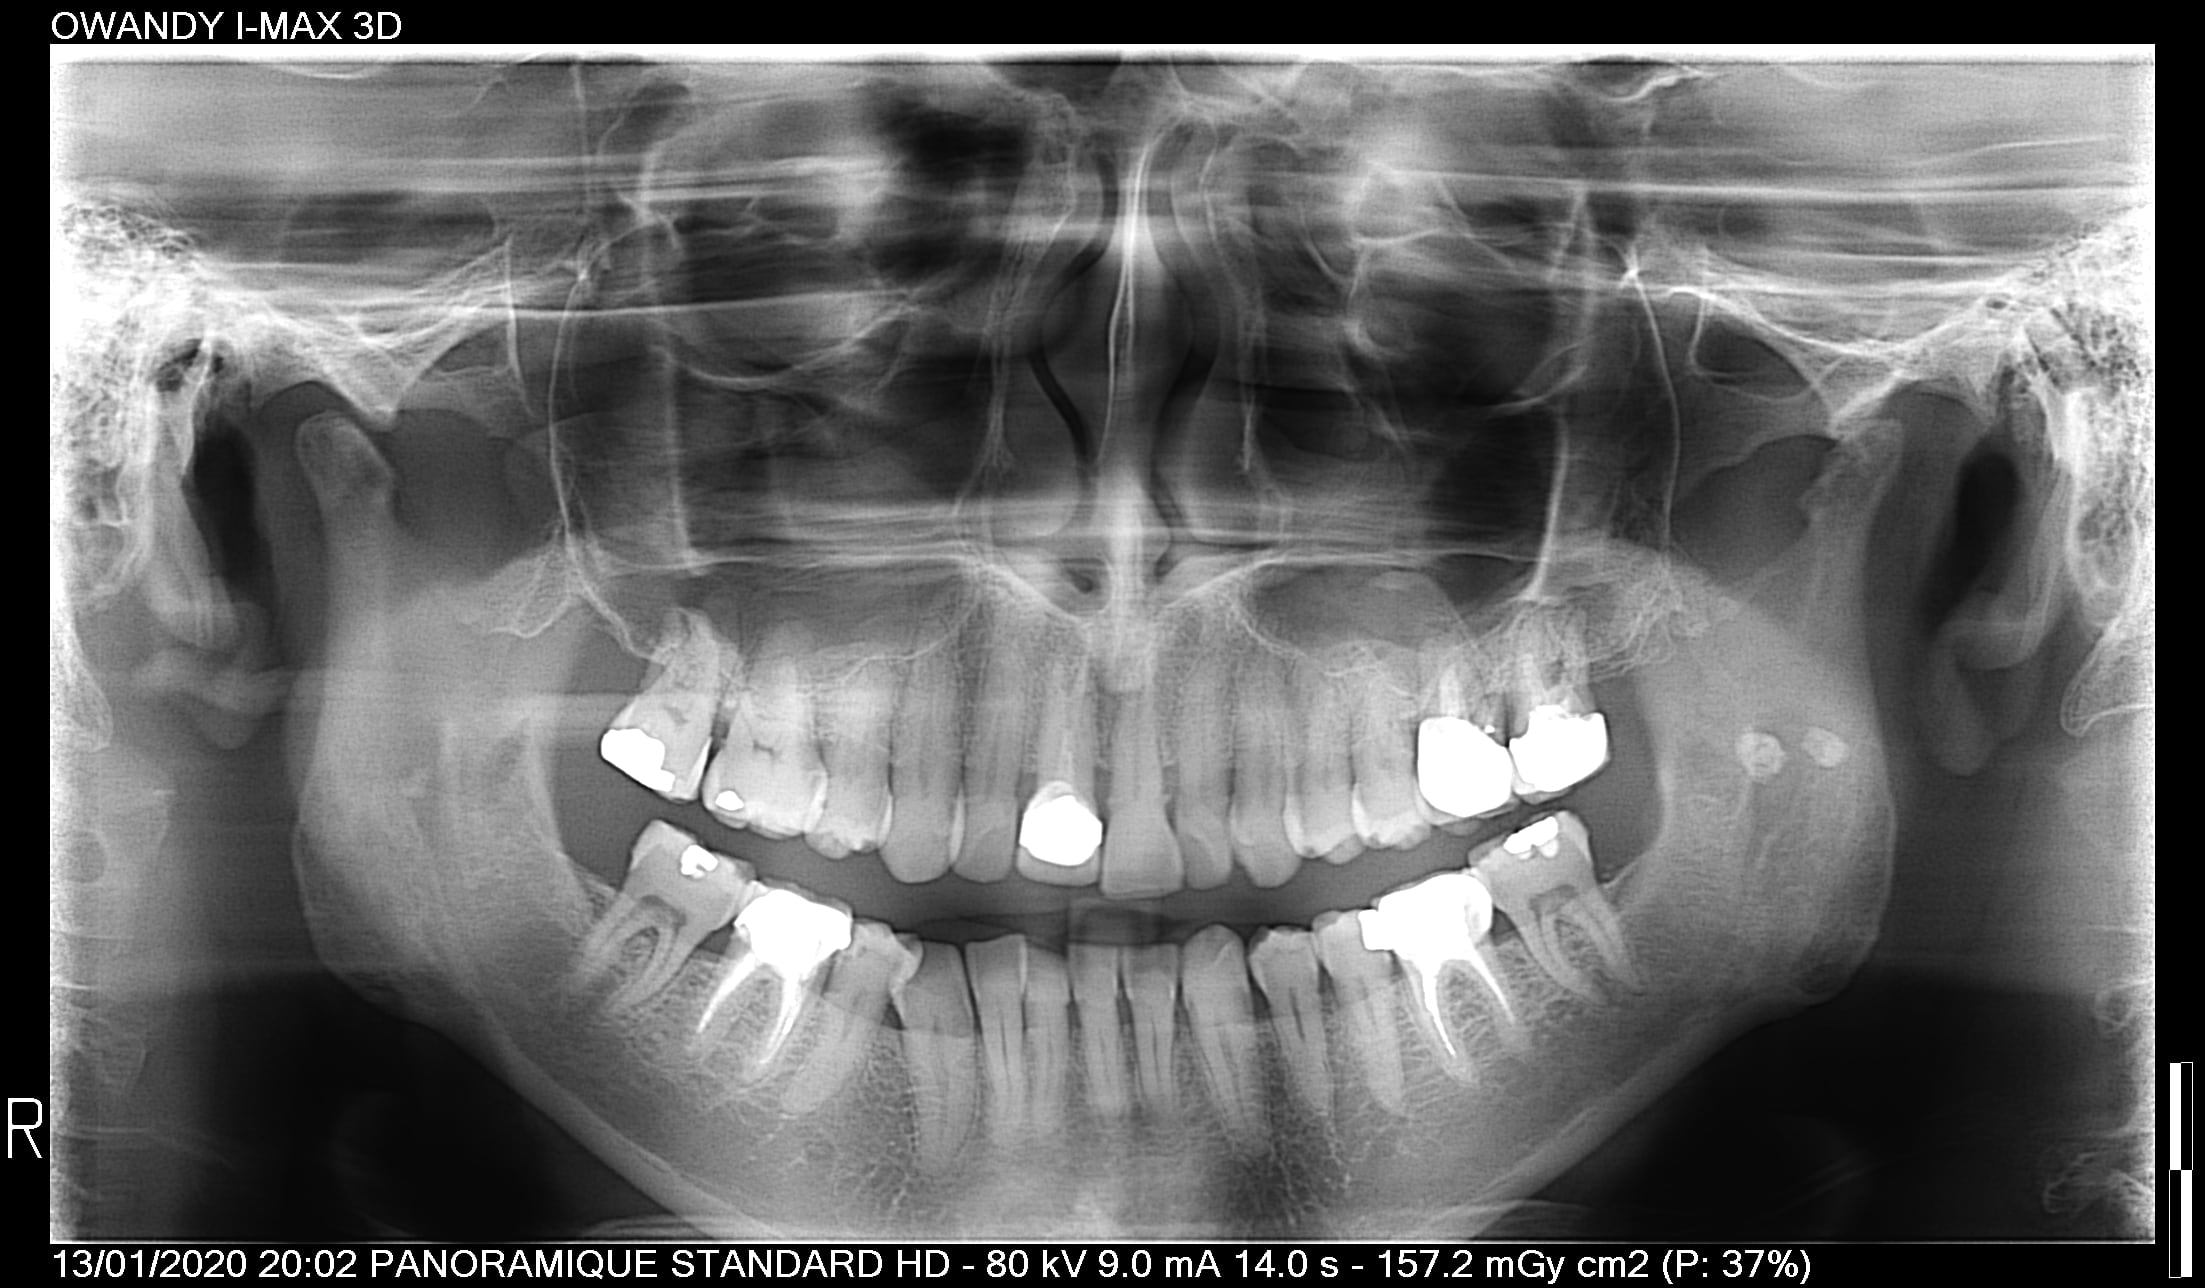

sur la 27 il y un kyste sur une sur occ qui a tendance à faire descendre la 7 à tous les coups .

peu importe ç est un pb de decalage lateral ,

donc le ttt ç est depose de 26+27 et prov sur uniquement 26 ( puisque la 27 est niquée pour le moment ) ,

limage de canine 13/43 pour donner de l aisance et du guidage plus souple à la fermeture .

pcq tu remarqueras que sont atm gauche est frit bouilli ,

Heu ... c'est quoi les 2 petites "boulettes " blanches dans la branche montante gauche ??

Spontanément, j'aurais dit calcifications parotide.

Comme enlaye mais il faudrait peut-être vérifier la présence de contacts non travaillants dans les latéralités notamment au niveau des éléments prophétiques 36 et 46.

Par ailleurs on note un espace entre les 17 et 16 ce qui pourrait être la résultante d'un appui trop marqué au moment de la fermeture, d'où décalage de la mandibule dans la fermeture.